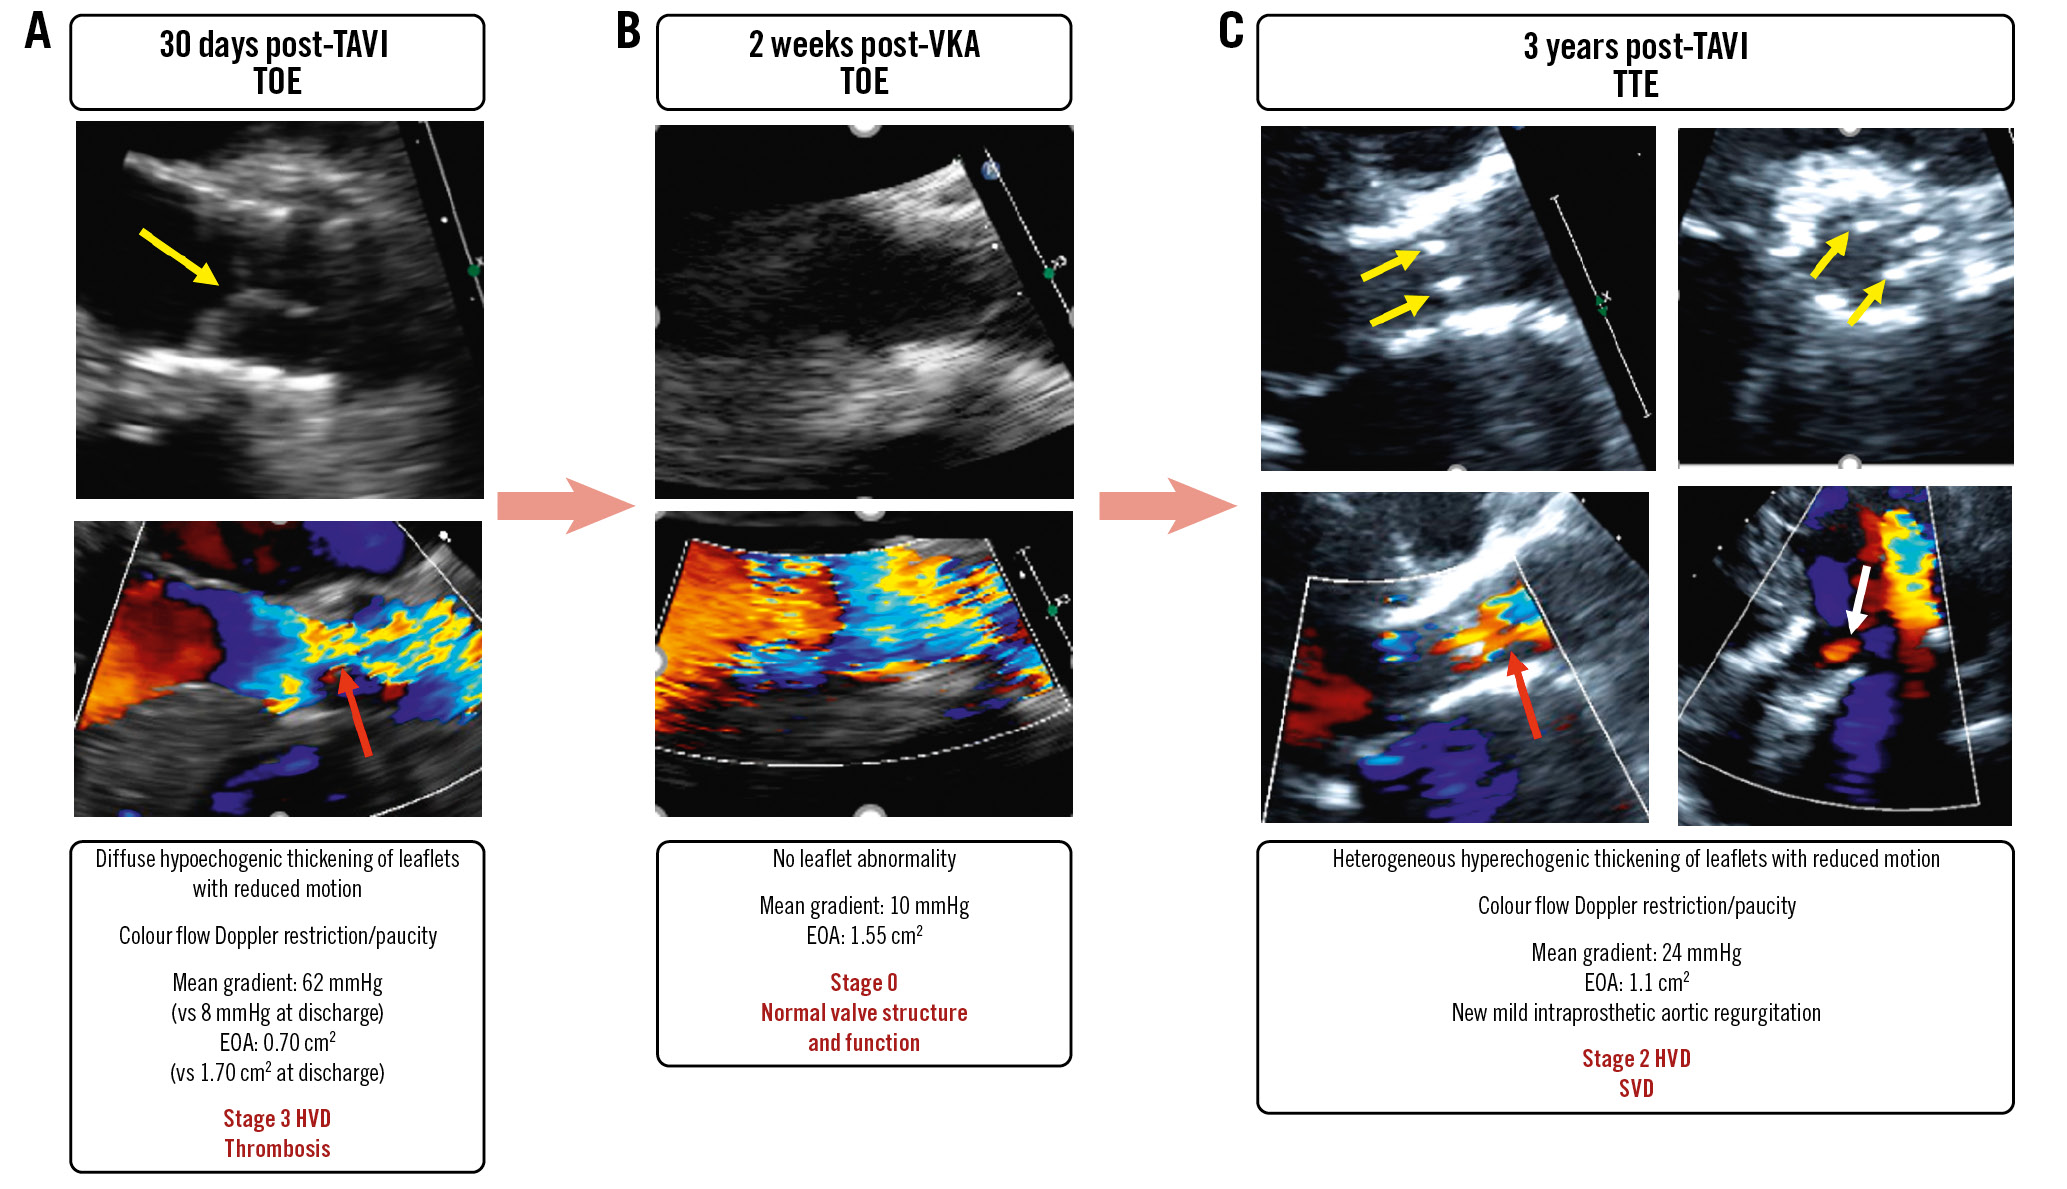

Figure 3. Representative examples of the different stages of bioprosthetic valve dysfunction and proposed management. Yellow arrows indicate valve thickening and reduced motion; red arrow: colour Doppler flow restriction and turbulence; white arrow: colour Doppler flow paucity. AR: aortic regurgitation; HVD: haemodynamic valve deterioration; MG: mean gradient; TTE: transthoracic echocardiography

Figure 5. A case of early valve thrombosis followed by accelerated structural valve deterioration. A female patient aged 73 years underwent TAVI with a SAPIEN XT 23 mm. At 30 days, she presented with clinical valve thrombosis resulting in severe (Stage 3 HVD) bioprosthetic valve stenosis (A). There was a quasi-complete resolution of the valve thrombosis and stenosis following 2 weeks of VKA treatment (B). However, 3 years later there was evidence of structural valve deterioration resulting in moderate (Stage 2 HVD) bioprosthetic valve stenosis (C). Yellow arrows indicate valve thickening and reduced motion; red arrows: colour Doppler flow restriction/paucity; white arrow: intraprosthetic aortic regurgitation (AR). EOA: effective orifice area; HVD: haemodynamic valve deterioration; SVD: structural valve deterioration; TAVI: transcatheter aortic valve implantation; TOE: transoesophageal echocardiography; TTE: transthoracic echocardiography; VKA: vitamin K antagonist

Step 3 of the algorithm presented in Figure 2 consists of staging the severity of the structural and haemodynamic valve deterioration (Table 3, Figure 3). This staging classification is based on the presence and magnitude of changes in the leaflet morphology and valve haemodynamic performance at TTE follow-up. It can be applied to BVD related to SVD, valve thrombosis, or valve endocarditis but not to non-structural BVD, such as PPM, where the BVD is already present at the outset of the TAVI or SAVR procedure and generally does not change during follow-up.

Stage 1: SVD is defined as the occurrence of abnormalities of valve leaflet morphology (leaflet thickening, fibrocalcific remodelling, tear or prolapse) and mobility during follow-up (Table 3, Figure 3)45. CT valve leaflet calcium density (calcium score/aortic annulus area) can be used as an early and sensitive marker for Stage 1 valve deterioration, and a density >58 Agatston Units (AU)/cm2 has been shown to be a powerful predictor of outcomes8. Stage 2: moderate HVD is defined as the presence of Stage 1 plus a moderate increase in the mean gradient from early postprocedural TTE to follow-up TTE with a concomitant decrease in EOA and DVI and/or new onset or worsening of intraprosthetic aortic regurgitation. Stage 3: severe HVD is defined with the same parameters as for Stage 2 but with more severe criteria.